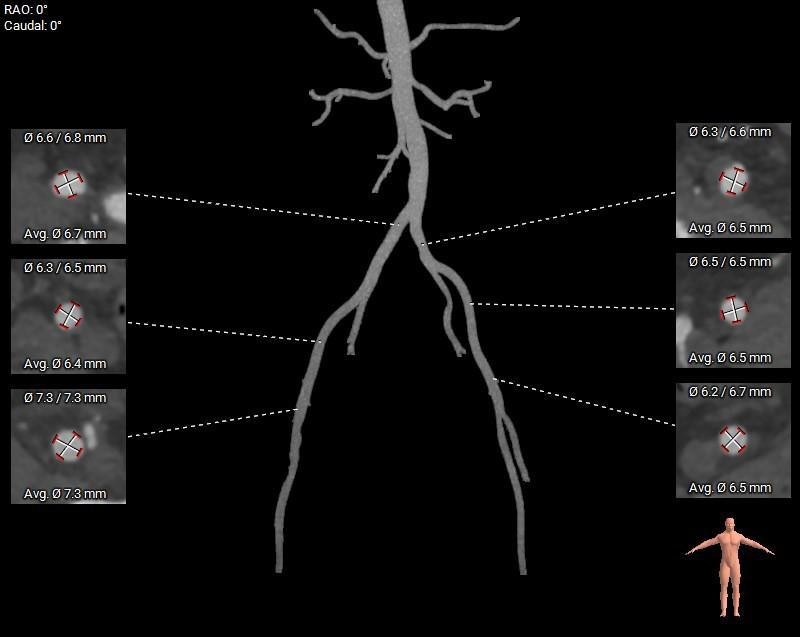

1.主动脉瓣瓣环周长90.9mm,平均周长径28.9mm。

4.横位心,主动脉弓宽度偏小及角度锐角。双侧血管内径可,符合血管入路条件。

外周入路: